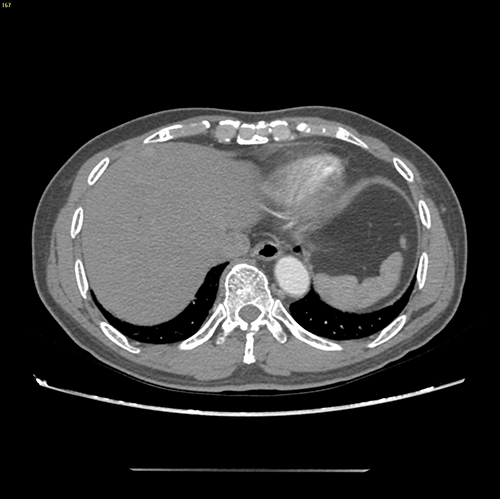

S58 肝癌--腹腔镜S58部分切除